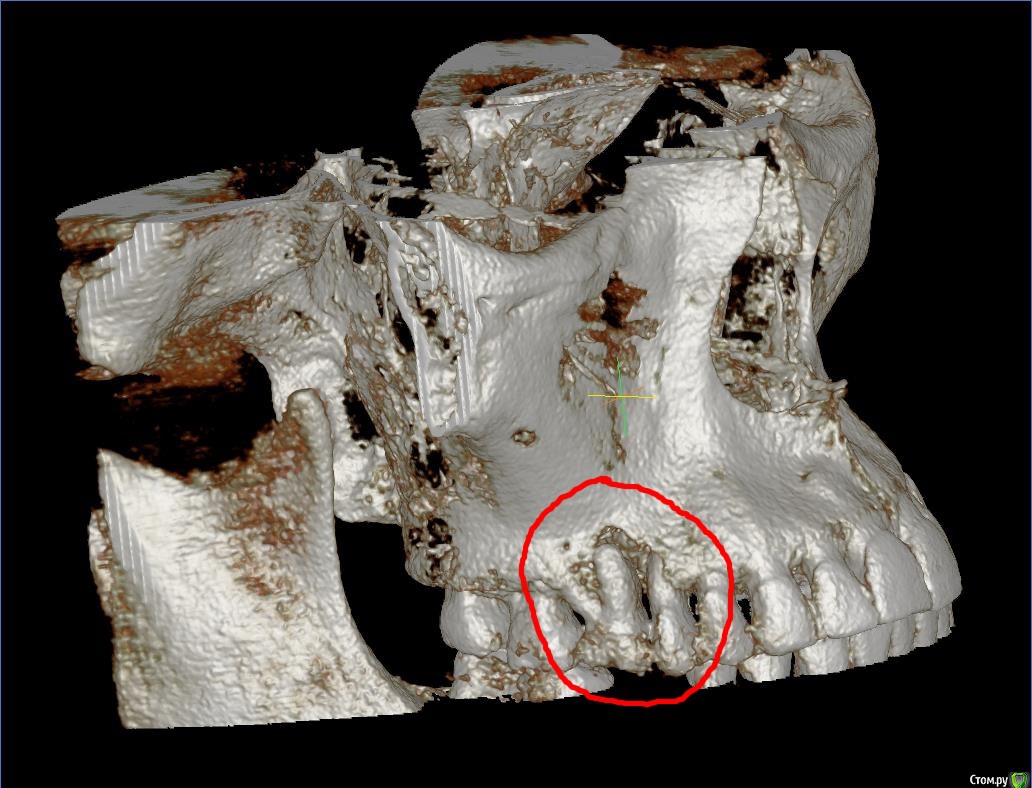

Faramir Опубликовано 18 апреля, 2019 Поделиться Опубликовано 18 апреля, 2019 (изменено) Сделал КТ. По 3D виду появился вопрос. Что это за разряжение кости в области шестерок на 3D виде КТ? Это нормально для КТ в этом месте или идет патологический процесс? Также интересно восстановится ли тут кость после удаления или лечения? Над левой шестеркой есть свищ над которым периодически вырастает и лопается белый шарик. Десна у правой шестерки за месяц дважды воспалялась, появлялась припухлость в виде валика, но после полосканий в течении 3 дней проходила. Можно ли спасти эти шестерки перелечив каналы или нужно удалять? У них в корнях стекловолоконные штифты на которые приклеены коронки/накладки наверное из керамики. Заранее спасибо за ответы. Изменено 18 апреля, 2019 пользователем Faramir Ссылка на комментарий